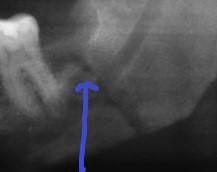

これは非常にまれですが、最も多いのが下顎です。抜歯をしている歯科医は、歯を引き出すためにある程度の圧力をかける必要がありますが、歯の周辺の骨の構造が壊れやすくなっていることを歯科用X線(パノラマ、CT)で把握します。

上顎の歯は、副鼻腔に近接している場合、パノラマ、CTで、歯の根が事実上鼻洞にあるように見えることがあります。これは通常、歯の根から洞を分離する細い骨があるために発生しません。しかし、時には抜歯中に穿孔が起こる場合があります。穿孔した場合は、空気が鼻から鼻腔に突入し、穿孔によって口に突入するため、吸い込んだ反射を避ける必要があります。穿孔が起こる場合、患者は特定の指示します。